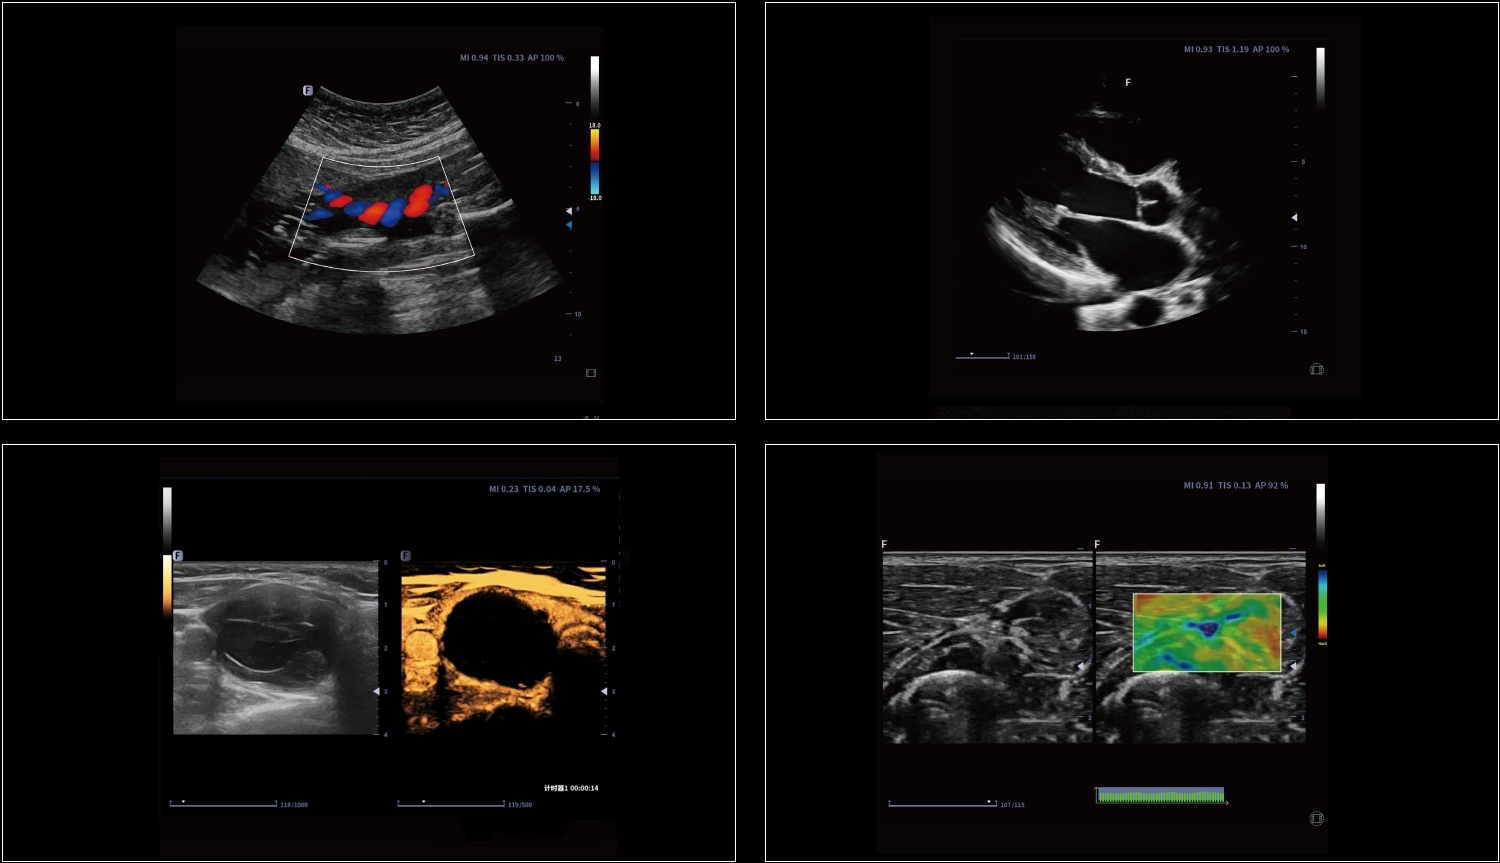

Technologia obrazowania ultrasonograficznego z inwersją impulsów i kontrastowaniem pozwala dokładnie wyodrębnić drugi harmoniczny kontrastowych mikropęcherzyków, co umożliwia uzyskanie obrazowania z wysokim stosunkiem kontrastu do tkanki oraz zapewnia bardziej szczegółową diagnozę kliniczną.